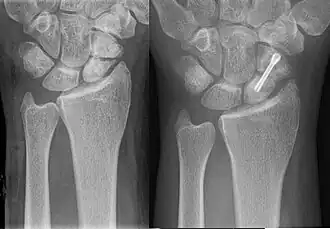

An X-ray showing a fracture through the waist of the scaphoid

Scaphoid pseudarthrosis, before and after treatment with Herbert screw.